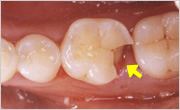

- チッピングやフラクチャー(破折)

- 奥歯の歯冠破折